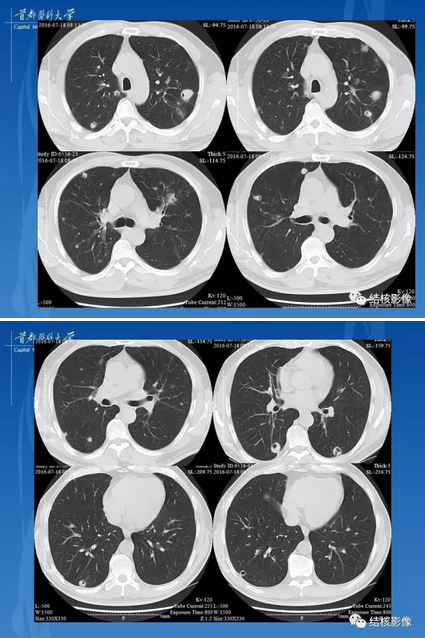

变态反应性肉芽肿性血管炎(css) 肺ct肺窗

图片尺寸1258x1191